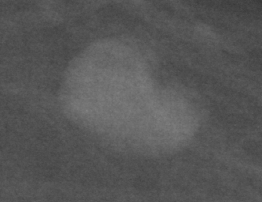

In our experiments, we use the Digital Database for Screening Mammography (DDSM) [4], a collaboratively maintained public dataset at the University of South Florida. It comprises approximately 2500 studies each containing both mediolateral oblique (MLO) and craniocaudal (CC) views of each breast. Each image is grayscale and accompanied by a mask specifying the region of the pre-segmented mass if present. Examples of benign and malignant masses are shown in Fig. 1.